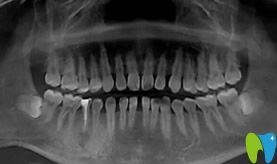

到后,鐘幫我拍了牙齒CT,牙縫問題從片子里可以看得很明顯了,你們說這么多年我是漏了多少財(cái)吧,簡直算不過來。我有時(shí)候想,這些年一直沒有存款,是不是都讓牙縫給漏掉了,哈哈,玩笑哈!

正畸前拍的CT影像: